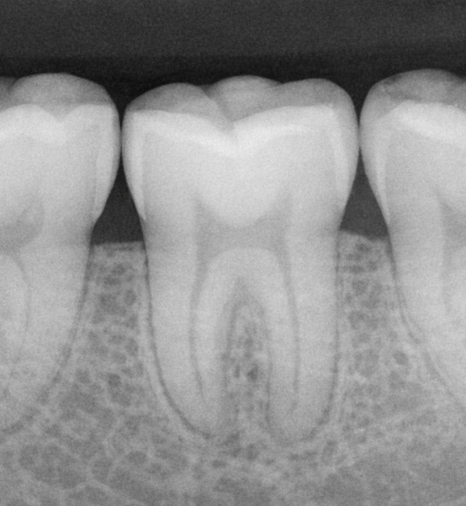

CTS가 까다로운 이유는

일반 X-ray로는 균열선이

거의 포착되지 않는다는 점에 있습니다.

이해를 돕기 위한 치아 균열 예시입니다.

균열의 방향이 방사선이

투과하는 방향과 평행할 경우

영상에 나타나지 않기 때문입니다.